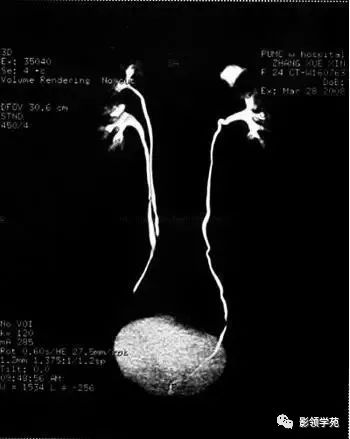

双肾盂畸形

右侧双肾盂畸形!